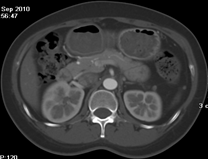

同一病人利用容積數(shù)據(jù)進(jìn)行三維處理后,高品質(zhì)MPR和三維圖像上則清晰顯示了縱向排列的腹腔干與腸系膜上動(dòng)脈相鄰近,血管發(fā)生變 異,近端血管閉塞,為臨床提供了精確的診斷信息。